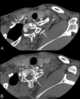

Sprengel's deformity (also known as high scapula or congenital high scapula) is a rare congenital skeletal abnormality where a person has one shoulder blade that sits higher on the back than the other. The deformity is due to a failure in early fetal development where the shoulder fails to descend properly from the neck to its final position. [Source: Wikipedia ]